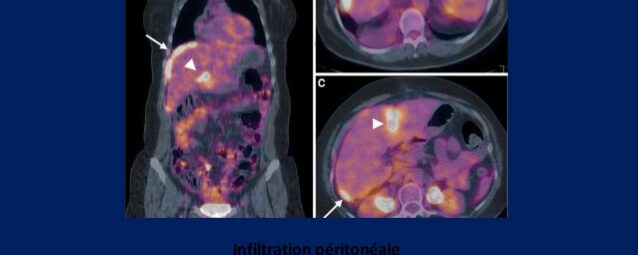

Carcinose péritonéale

Fiche mémo carcinose péritonéale pour rebondir sur l’atelier acomen des JFMN 2017